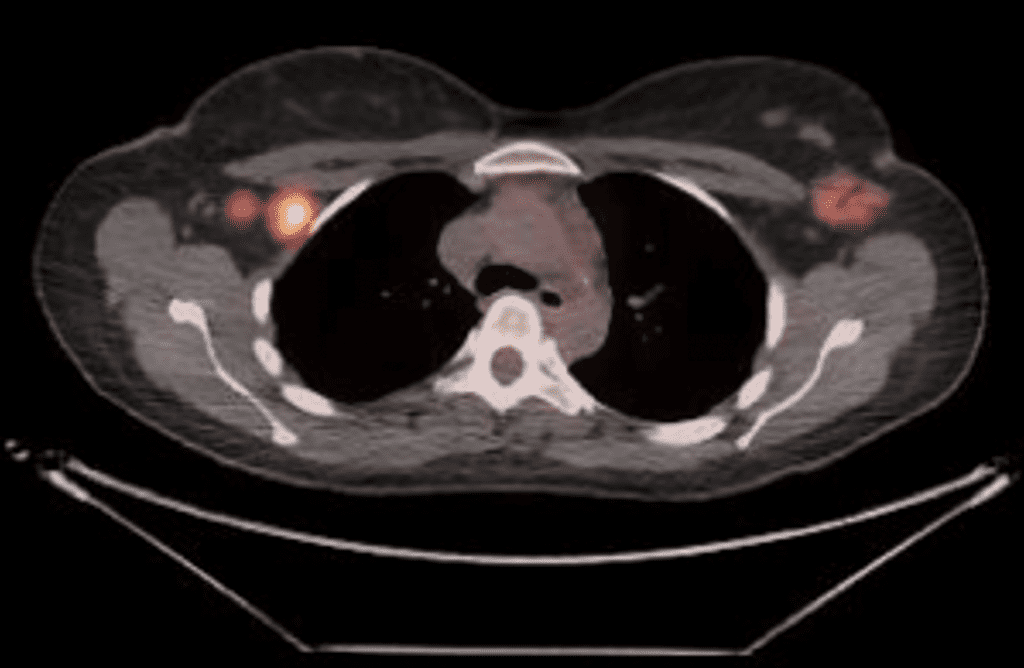

After initial diagnosis, patients will often be recommended to undergo systemic staging (looking for any cancer elsewhere in their body).  This is performed with a single PET CT scan or a plain CT of the lungs and abdomen/pelvis combined with a bone scan.

A PET CT requires 12 hour separation of baby/mom due to external radioactivity, but the milk itself is safe to give as FDG (the IV agent given to localize cancer) is not excreted in breastmilk.

Staging PET CT showing a right breast tumor, right lymph node involved with cancer, and a left breast area of “avidity” during lactation. This left breast area was biopsied and showed lactational changes only.